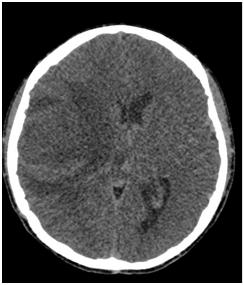

We present the case of a 16-year-old male patient, born in Veracruz Mexico with history of pulmonary stenosis, hypoplastic right ventricle, interauricular communication and patent ductus arteriosus who had surgical intervention with Blalock Taussig shunt on November of 2003. On July 11th 2016 he started with numbing of the left half of his face including the tongue, for which he didn’t seek any medical attention. On July 18th 2016 he had a generalized seizure, which lasted 10 minutes, according to his family. On July 28th 2016 he started to lose strength of the left half of his body and wasn’t able to walk or move his left arm. With these symptoms he was admitted to our hospital where he also referred headache. CT scan showed hypodense images on right temporoparietal region and reinforcement images on right parietal region suggesting brain abscesses (Figure 1 & 2). With these findings, along with the clinical presentation, the diagnosis of brain abscess was made and antibiotic treatment was started with third generation cephalosporin, metronidazole and glucopeptide. The patient was evaluated by the neurosurgery team who decided to differed surgical treatment because of the size of lesions in CT scan and improvement in next CT scan images. On August 8th 2016 a MRI (Figure 3) of the brain showed capsule formation. The patient continued with antibiotic treatment and dexamethasone in reduction dose. A new MRI of the brain, on August 29th 2016, showed abscesses of less than 3 cm, this along with the patient improving neurological state and decide no need for surgical treatment. The patient completed 61 days of parenteral treatment with ceftriaxone, metronidazole and vancomycin. The last imaging study previous to the discharge of the patient showed brain abscesses of less than 0.5 cm.

Figure 1

Figure 2